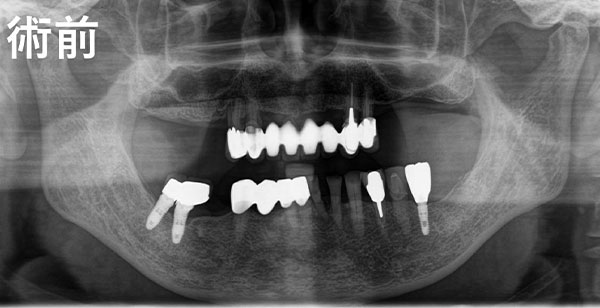

All-on-4は、骨のある部分を正確に選び、適切な角度でインプラントを埋入する高度な技術が必要です。当院では、歯科医師の「経験や勘」だけに頼るのではなく、確実なデータに基づくコンピューターガイデッド手術を行っています。

事前にCTデータを解析し、神経や血管の位置を完全に把握した上で、インプラントの埋入位置を0.1ミリ単位でシミュレーションします。これにより、外科的なリスクを最小限に抑え、長期的に安定する治療計画を立案します。

また、当院では手術本番までに最低でも3回以上のシミュレーション検証を重ねます。徹底的にルートを確認してから臨むため、実際のオペは「リハーサルを経た4回目」のような確実性を持って、スムーズかつ安全に行うことができます。